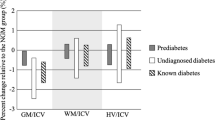

The volumetric meta-analysis demonstrated significant global reductions in total brain volume (Z = −2.77, p = 0.006), brain parenchymal fraction (Z = −7.77, p < 0.001) and grey matter volume (Z = −4.75, p < 0.001) (Table 3, Supplementary Figures 2 and 3). Regional reductions were revealed in orbitofrontal cortex grey matter (Table 3, Z = −3.29, p = 0.001), the hippocampus (Fig. 3, Z = −3.67, p = 0.0002) and basal ganglia (Table 3, Z = −2.61, p = 0.009). Reductions in frontal and temporal volumes approached statistical significance (p = 0.057 and p = 0.066, respectively) (Supplementary Figure 4). There were no significant differences in anterior cingulate, superior temporal, and parietal regions (Table 3).

Modifier analysis

Modifier analysis was only performed if there were at least 5 studies with complete data for a particular region. Reductions in total brain volume and the hippocampus in T2DM were robust to adjustment by age (Table 3), and age was a significant modifier of the differences between patients and controls in hippocampal volume, with studies that included younger patients showing more marked reductions between patients and controls than those including older participants (modifier effect Z = 6.2, p < 0.001).

Hypertension was associated with more pronounced differences in frontal volumes between T2DM patients and controls: studies where a higher proportion of patients with T2DM had comorbid hypertension reported smaller frontal volume in T2DM relative to controls (modifier Z = −2.51, p = 0.012). There were no significant effects of gender or age on frontal reductions. For total grey matter volume, hypertension as a modifier of the differences between patients and controls approached statistical significance (modifier Z = −1.89, p = 0.058), whereas age, gender or HbA1c did not modify these differences. For hippocampal volume, neither hypertension nor glycemic control (using HbA1c as a proxy measure) modified the differences between patients and controls, though again data were limited and between-study differences in HbA1c relatively small.